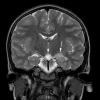

NEOPLASMS (NEURONAL)

Multinodular Vacuolating Neuronal Tumor (3)